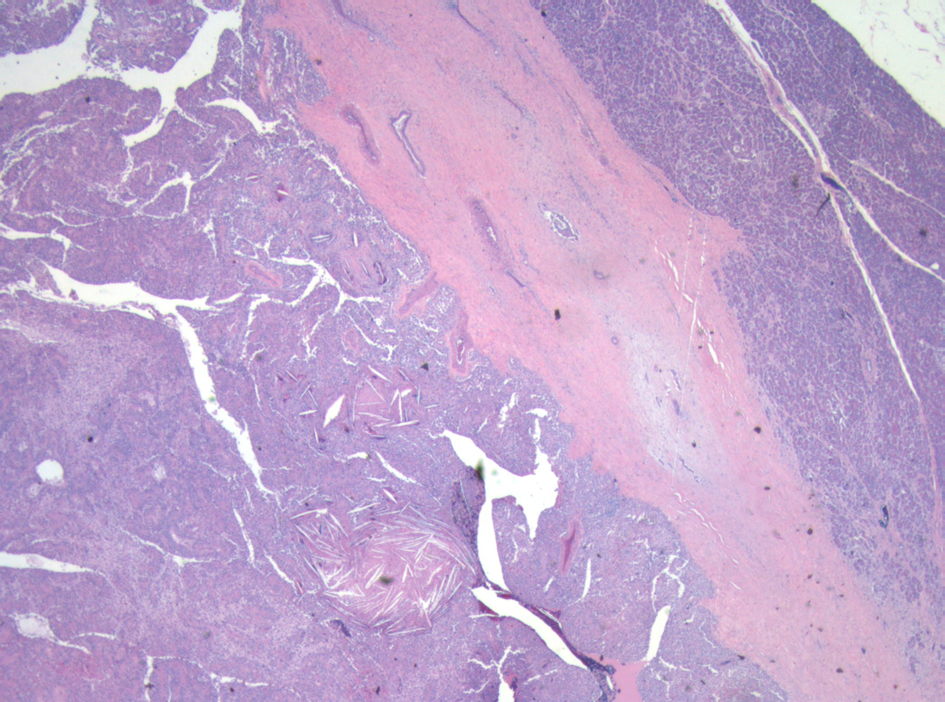

Surveillance AUS was performed biannually, then annually. A surveillance AUS performed 43 months post-operatively demonstrated fatty transformation of the liver with a discrete hypoechoic lesion measuring 1.1 × 1.0 × 0.8 cm in segment 4B/5 of the liver. There was no evidence of local recurrence. The patient was asymptomatic, with no focal findings on physical exam. Laboratory studies including liver function tests were within normal limits. Magnetic Resonance Imaging (MRI) demonstrated a 1-cm lesion in segment 4B, and a 0.8 cm lesion in segment 5 of the liver (Fig. 4). Both lesions demonstrated intermediate high signal on T2 weighted images and progressive enhancement after gadolinium injection. They demonstrated restricted diffusion on diffusion weighted imaging. They were suspicious for metastases, but atypical hemangiomas remained in the differential. In order to narrow this differential, a contrast enhanced ultrasound study was performed, and the lesions demonstrated mild arterial enhancement with rapid complete washout in keeping with metastases. These lesions were not avid on Fluorodeoxyglucose-Positron Emission Tomography (FDG-PET). The patient underwent for a diagnostic laparoscopy and US-guided biopsy of her hepatic lesions. A definitive diagnosis could not be made intra-operatively based on intra-operative frozen section analysis of the needle biopsy, however the pathologist favored malignancy rather than a benign etiology. Therefore, the procedure was converted to a laparotomy with resection of segments 4b and 5, as well as a cholecystectomy. An enlarged periportal lymph node was excised as well. Pathology revealed 2 foci of metastatic solid pseudopapillary tumor of the pancreas in the liver (Fig. 5), measuring 8 mm and 7 mm. The enlarged lymph node was negative for malignancy. She recovered uneventfully from this procedure and was discharged home on POD 5.

![]() Click for large image | Figure 4. MRI with gadolinium contrast demonstrating a metastases in segment 4 of the liver. |